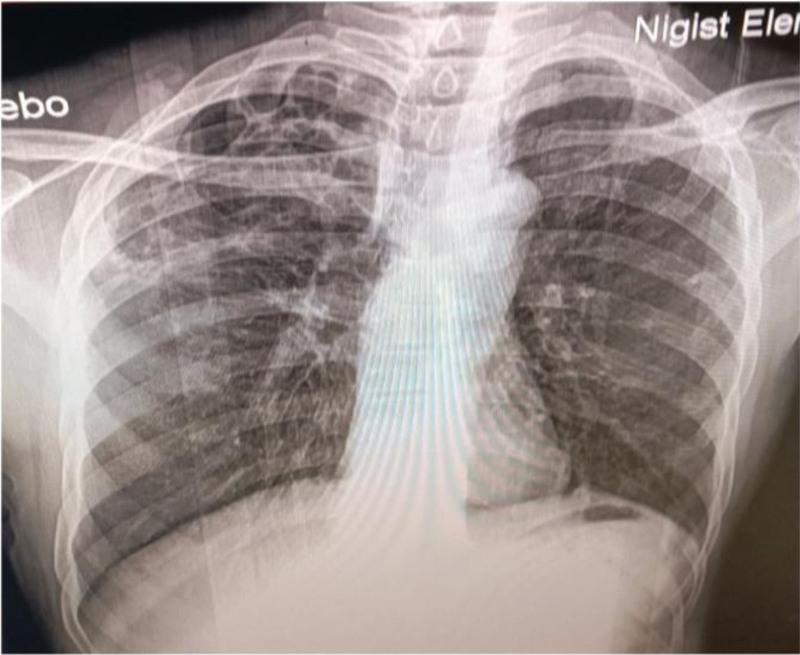

A 55-year-old man presented with neck pain and swelling that had persisted for 1 week, following 2 weeks of blunt trauma to the head and neck, which resulted in several superficial abrasions due to his poorly managed epilepsy. Imaging studies revealed thrombosis in the left IJV, accompanied by an abscess that extended into the sternocleidomastoid muscle. Gram staining of the specimen obtained from the neck abscess confirmed the presence of Streptococcus bacteria.

The presence of a thrombus in the IJV following blunt trauma to the head and neck, along with a nearby soft tissue abscess, suggests a diagnosis of LS. However, this case is atypical due to the unusual preceding event of blunt trauma and the identification of a rare pathogen, specifically Streptococcus bacteria.